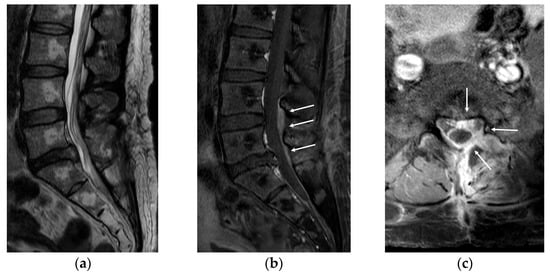

Five days after surgery, she complained of severe pain in her left lower extremity again. Following wound exploration with additional laminectomy, revealing no significant compressive lesion except epidural fibrosis, the symptom improved. Six days after revision surgery, she complained of gradually increasing pain in her left lower extremity, followed by profound weakness (no voluntary movement in the left ankle and big toe dorsiflexion and ankle plantarflexion). Revision surgery revealed severe epidural fibrosis along the thecal sac and L5–S1 roots (left side dominant). Normal dura was identified after peeling the thick epidural fibrosis (Figure 3). Pain and weakness of the left extremity disappeared immediately after surgery. However, two additional surgeries were needed due to the same pain and weakness episodes, several days following the surgeries. Operative findings were also similar to that of the previous surgeries with severe epidural fibrosis around the thecal sac and nerve roots. Symptoms were also alleviated immediately after surgery. Postoperative steroid therapy or narcotics did not work at all. Laboratory and culture studies documented no evidence of infection or rheumatoid disease. Finally, we performed L4–S1 oblique lateral interbody fusion (OLIF) with hyperlordotic cages to ameliorate tethering and traction of the thecal sac and nerve roots through posterior column shortening (Figure 4). Pain and paresthesia were considerably decreased. Weakness was also reduced. Eventually, the patient was able to walk again following six additional surgeries over 11 weeks. After the final surgery, postoperative wound infection by Candida albicans was identified, and treated successfully with antifungal agents. Follow-up MRI at 6 months postoperatively showed a well-decompressed thecal sac and nerve roots. However, roots were clumped and distorted within the thecal sac, suggesting arachnoiditis (Figure 5). Fortunately, her pain in the leg was considerably reduced, without neurological deficits. At the final follow-up, she was doing well with oral medication without taking narcotics (VAS 3) over the 2 years postoperatively.

Figure 5.

(a,b) Magnetic resonance imaging at 6 months postoperatively showed a well-decompressed thecal sac and nerve roots. However, roots were clumped and distorted within the thecal sac, suggesting arachnoiditis.